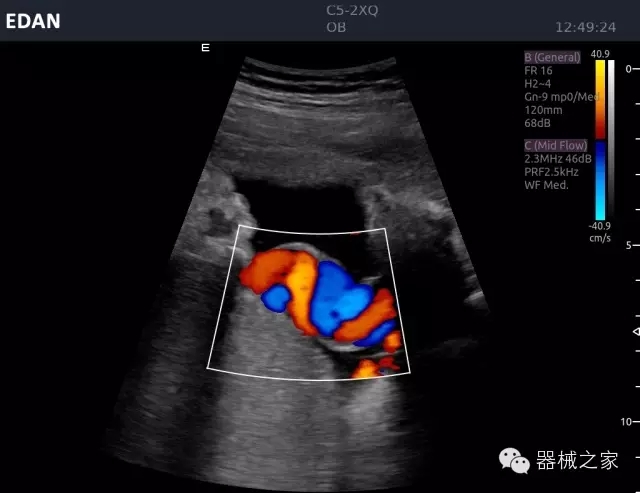

經(jīng)典產(chǎn)品:Acclarix AX8

臨床圖片賞析

睪丸低速血流

臍帶血流

頸動脈頻譜